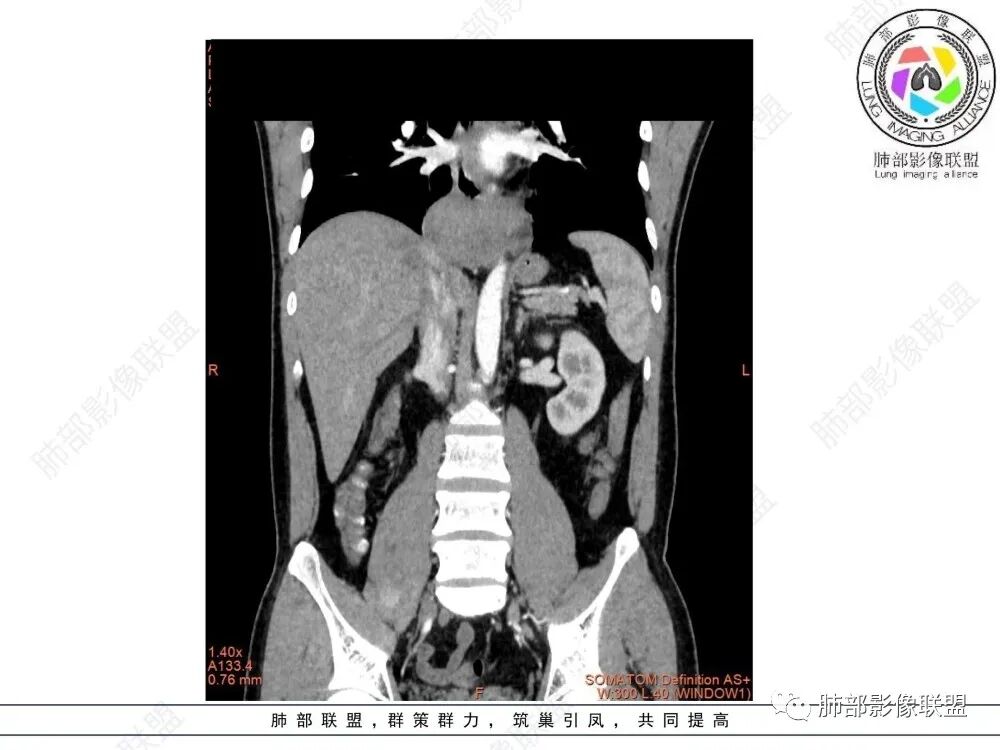

影像学特点:类纵隔区病变,沿食管生长,形态不规则,但边界清楚,内部信号/密度均匀,强化程度比较弱。

影像诊断思路:起源食管肿瘤(非黏膜起源,肌层起源),良性或低度恶性肿瘤可能性大,一般以神经鞘瘤、胃肠间质瘤及平滑肌瘤为主。食管神经鞘瘤强化明显均匀、以食管上段多见,周围常见炎性增大淋巴结,不太符合;胃肠间质瘤小的比较均匀,大的不均匀,但强化程度较高;影像上看这例病例比较符合平滑肌瘤。

食管平滑肌瘤是最常见的食管良性肿瘤,多见于男性,男女之比为2.6:1,高发年龄 30~60岁之间与食管癌相比,食管平滑肌瘤 的一个主要特点是病史相对较长,病情进展缓慢。病史最长者达10年余,平均 15.7个月,尽管病史较长,但大多数患者仍能进普食。食管平滑肌瘤的诊断一般比较容易,结合患者临床症状、食管造影及食管镜所见,一般均能得出正确诊断。食管造影主要为充盈缺损,病变与食管壁成锐角,粘膜线连续无破坏,管腔收缩扩张比较自如。钡餐造影敏感性高,但对食管壁间及食管周围情况难以判断。CT具有极高的密度分辨率,并且可以获得高质量的多平面重组图像,有利于食管壁间及食管周围情况的判断,表现为食管下段环绕管壁生长,偏心性或薄厚不均软组织密度肿块,密度均匀,内缘分叶状,管腔与正常食管壁构成不规则多角形扩张,增强动脉期无强化,多角度重建其病灶长轴与食管长轴不一致。由于食管壁在收缩状态下厚度约为5.6mm,扩张状态厚度不超过3mm,CT扫描时保持食管处于扩张状态可提高小病灶检出率。MR表现为T1加权等信号,T2加权稍高信号,可见高信号粘膜层,增强扫描轻度渐进性强化,密度均匀,无出血坏死。对于粘膜及周围脂肪间隙的判断具有明显优势。